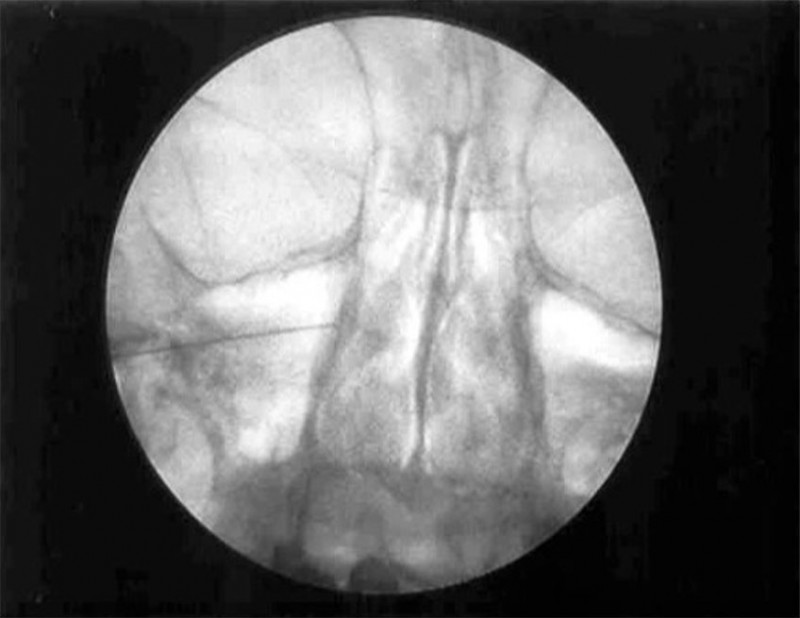

El paciente se coloca en decúbito supino. Con una proyección lateral del arco de rayos se localiza el angulo mandibular, de manera que podamos obtener una proyección lateral pura, se elimina el doble contorno mandibular, una vez conseguida esta proyección también se elimina la posibilidad de visualizar dos fosas en la proyección. En este momento se procede a fijar la cabeza del enfermo a la mesa quirúrgica. Con la proyección lateral se localiza la fosa pterigopalatina del lado a tratar En esta proyección se deben localizar la silla turca, el clivus y el seno esfenoidal. La fosa pterigoideapalatina se encuentra en la parte anteroinferior del seno esfenoidal, teniendo una forma de coma, situándose el ganglio en el tercio superior de la misma. Una vez localizada la imagen radiológica, se sitúa una varilla metálica que se superponga longitudinalmente con la fosa y se marca una línea en la piel que coincida con la barra. En el punto donde esta línea se cruza con el borde inferior del arco zigomático tendremos el punto de entrada. Se llega a la fosa a través de la escotadura mandibular y la fisura pterigomaxilar. Esta técnica no se puede realizar en visión túnel, pues se interpone el arco zigomático, por lo que tendremos que dirigir la aguja ligeramente superior y anterior, hasta que choquemos con hueso. A continuación recolocamos los rayos en visión anteroposterior comprobando la situación final de la aguja por dentro del borde de la fosa nasal, por encima del cornete medio.